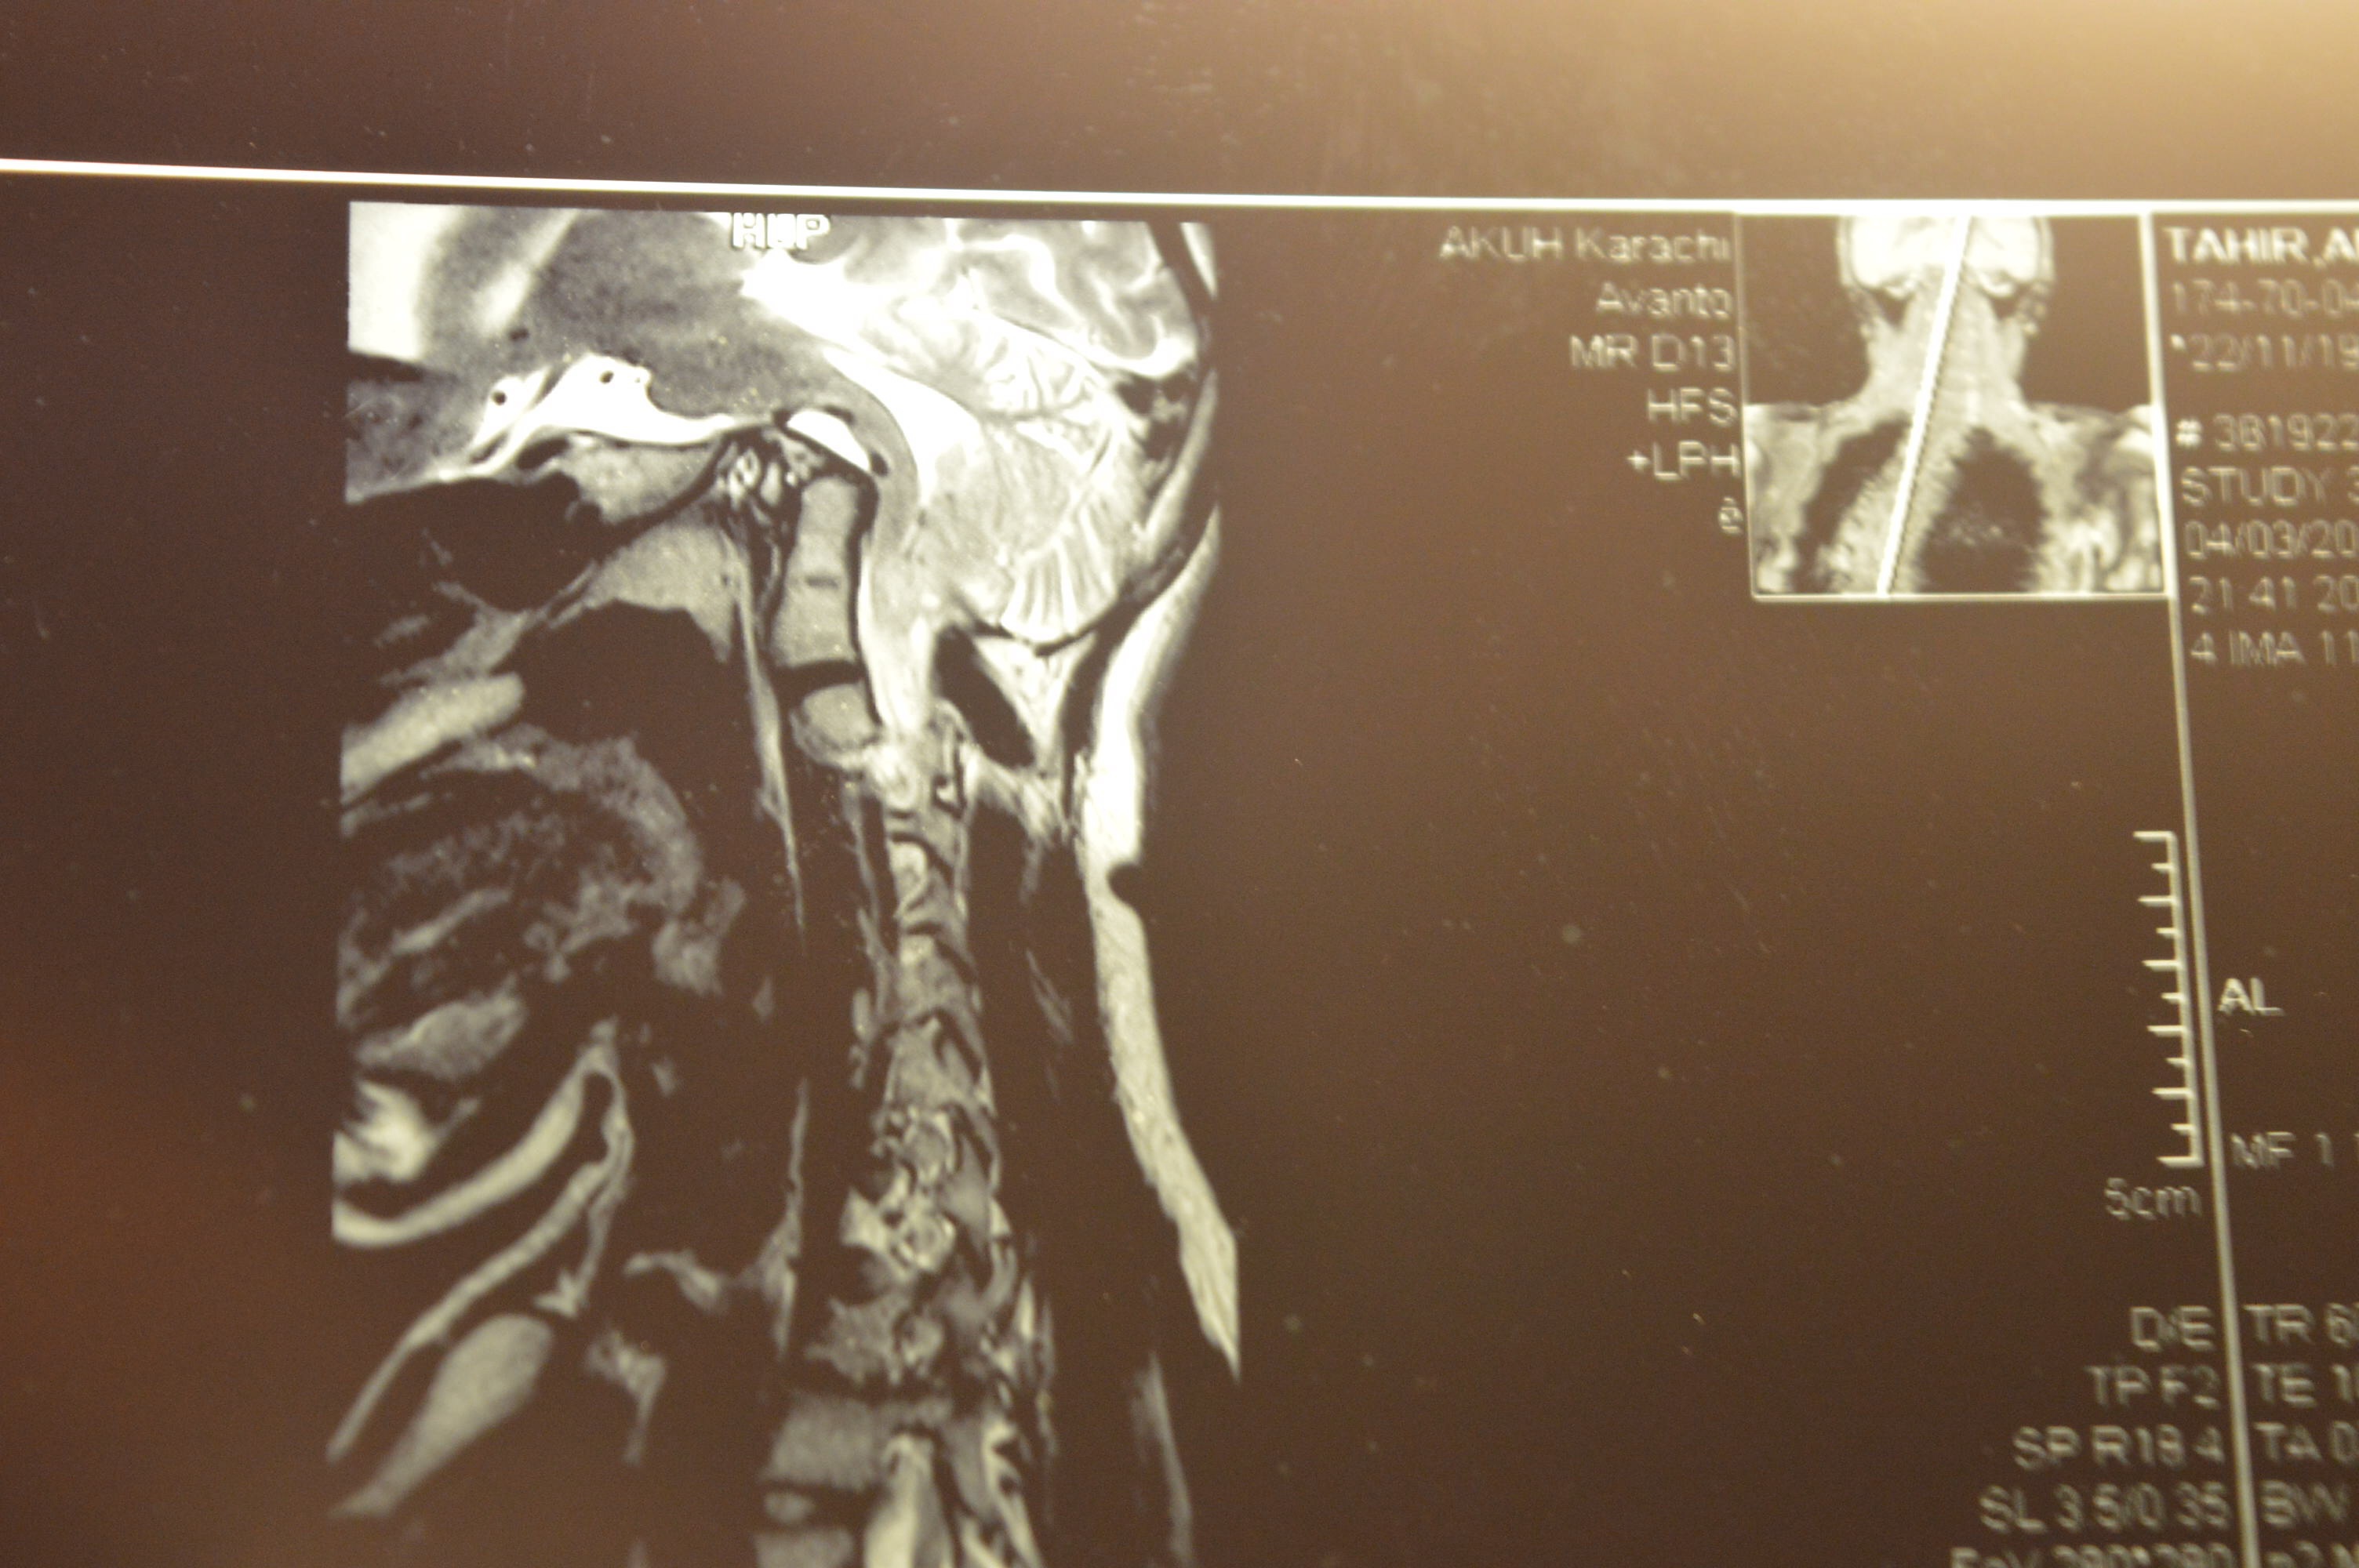

My daughter Aneesha has B.I and she has to undergo surgery for scoliosis…Her spine surgeon does not want to do the correction as she Has BI and he is afraid that this will be dangerously fatal.I would really appreciate if anyone here can share their experiences in BI…if anyone here has BI? How to deal with it in your daily life and any personal experiences about living with it…please , do help me…

So grateful for your guidance.Aneesha underwent a duro Plasty last year and her syrinx is dissolving now…to a nearly 40%…This was the requirement of her spine surgeon.But when he took her to the theatre his neuro surgeon pointed it out to him that it was dangerous to operate on her spine because of her BI…now he says he will not do it until the BI is addressed…though her original neuro surgeon says that it’s ok to go ahead with the surgery even with the BI…but now even he isn’t sure…this is so unnerving…Though Aneesha really doesn’t have the BI symptoms that I read hear…except for the sleep apnea and Hydrocephallus which developed after the duro Plasty…and walking issues because of the scoliosis and lumber lardosis…

Have you had surgery for BI and what are your symptoms? Do you wear this collar all the time?Is it possible for you to post an X-Ray of your cervical spine so that I can maybe see your extent of BI and compare it with Aneeshas and show it to her surgeon?